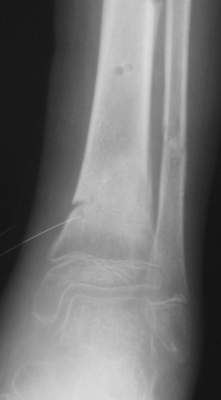

В январе 2005: варусная деформация н\3 голени, болевой с-м, комбинированная контрактура г\стопного сустава, нейропатия м\берцового нерва сохраняется слабость разгибания 1 пальца.

Операции: 1 Клиновидная резекция на вершине деформации м\берцовой кости.

2 Тугоподвижный ложный сустав н\3 б\берцовой кости. Рубцы выполняющие пространство между отломками, канал проксимального отломка иссечены.

Одномоментное устранение деформации, остеосинтез Г-образной пластиной.

Пластика по Хахутову.

Заживление проксимальной части раны вторичным натяжением без нагноения. Рана зажила. Спицы удалены через 1,5 недели после операции.

Особого смысла в них не было.

Учитывая фон (интеллект, etc) гипсовая повязка.

На данный момент ходит при помощи костыля (без присмотра -без костыля :), разрабатывает движения в г\стопном суставе.